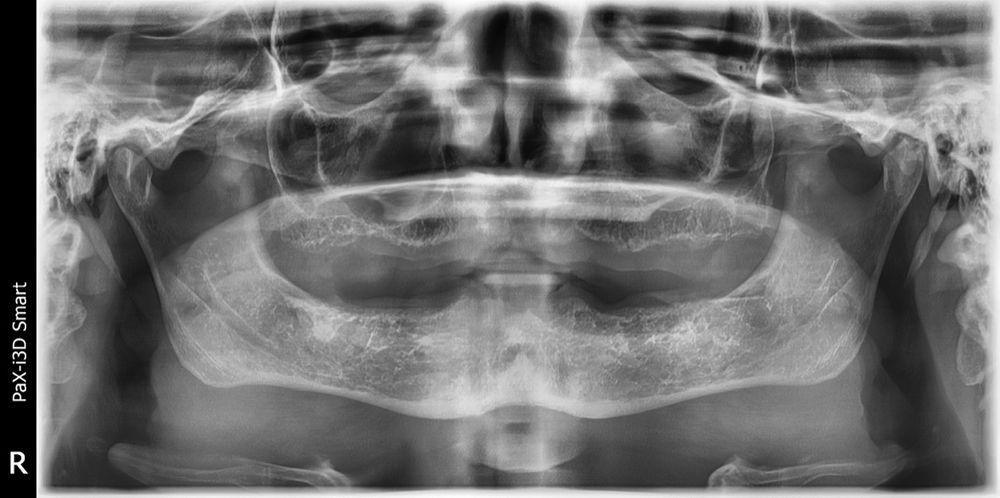

Author’s first case—a lady who hated her dentures and was willing to pay big for something fixed. At the time, Dr Gupta didn’t have a CBCT, but he had faith in his ability to place the implants where they belonged, based solely on the pan. Somehow, the maxillary sinus, especially on the right side, didn’t phase him, though he says now that it should have (Figure 1).